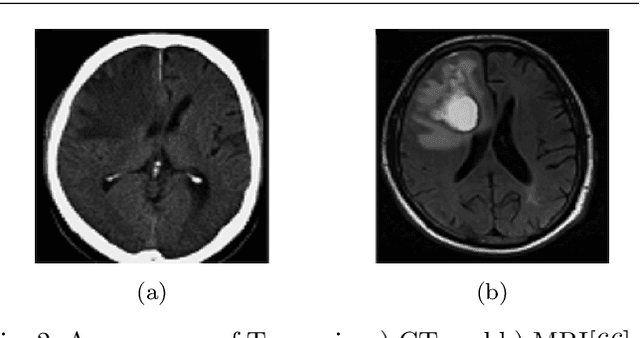

Glioma is the most deadly brain tumor with high mortality. Treatment planning by human experts depends on the proper diagnosis of physical symptoms along with Magnetic Resonance(MR) image analysis. Highly variability of a brain tumor in terms of size, shape, location, and a high volume of MR images makes the analysis time-consuming. Automatic segmentation methods achieve a reduction in time with excellent reproducible results. The article aims to survey the advancement of automated methods for Glioma brain tumor segmentation. It is also essential to make an objective evaluation of various models based on the benchmark. Therefore, the 2012 - 2019 BraTS challenges database evaluates state-of-the-art methods. The complexity of tasks under the challenge has grown from segmentation (Task1) to overall survival prediction (Task 2) to uncertainty prediction for classification (Task 3). The paper covers the complete gamut of brain tumor segmentation using handcrafted features to deep neural network models for Task 1. The aim is to showcase a complete change of trends in automated brain tumor models. The paper also covers end to end joint models involving brain tumor segmentation and overall survival prediction. All the methods are probed, and parameters that affect performance are tabulated and analyzed.